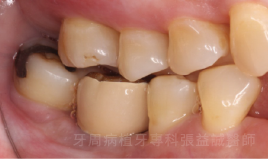

治療前 治療後

治療前

治療後